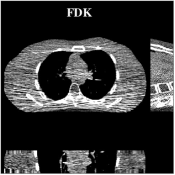

Recent works applied learned unions of transforms to other applications. For example, the union of transforms model was pre-learned (from a dataset) and used in a clustering-based low-dose 3D CT reconstruction scheme [26]. Fig. 4 shows an example of high quality reconstructions obtained with this scheme. While the work used a PWLS-type reconstruction cost, a more recent method [132] replaced the weighted least squares data-fidelity term with the shifted-Poisson likelihood penalty, which further improved image quality and reduced bias in the reconstruction in ultra low-dose settings. Other recent works combined learned union of transforms models with material image models and applied it to image-domain material decomposition in dual-energy CT with high quality results [137, 138].